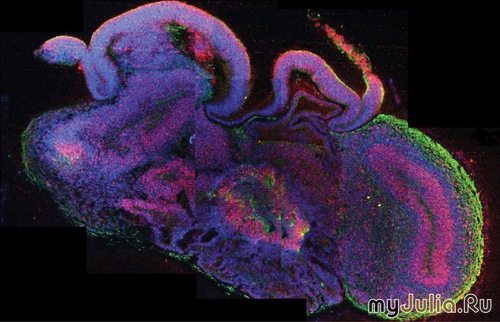

В истории есть примеры множества сумасшедших учёных, ставивших замечательные с точки зрения науки, но этически ужасные эксперименты на людях и животных. А сейчас новые «доктора Франкенштейны» благодаря этому сделали прорыв в медицине, хотя их опыты словно сошли со страниц научно-фантастических романов или ужасов. 1. Австрийские исследователи вырастили в лаборатории мозг

Исследователи из Австрии сделали большой шаг в области исследований мозга — они в буквальном смысле вырастив мозг. Радует то, что этот мозг не плавает в банке, скорее это «мозговые органоиды» всего 4 мм в диаметре, выращенные из стволовых клеток человека в чашке Петри. Этот так называемый мини-мозг представляет собой первый случай, когда учёные смогли создать что-то близкое к мозговой ткани в лабораторных условиях. Безусловно, до разумной сущности ещё далеко, но благодаря мини-мозгу удалось узнать, как развивается редкое заболевание под названием микроцефалия. Кроме того, подобные образцы можно использовать для диагностики и лечения других заболеваний вроде аутизма и шизофрении. 2. Норвежский врач вывел женщину из состояния клинической смерти